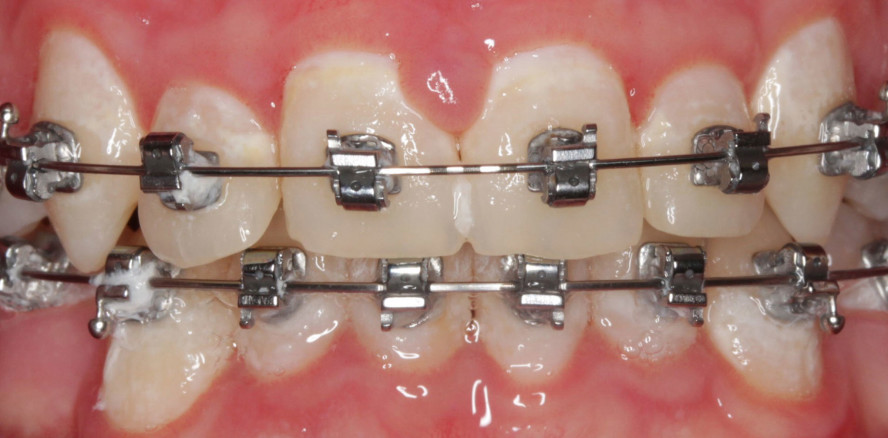

Dass nicht nur Schmelz, sondern auch häufig zahnärztliche Restaurationen einer harmonischen Zahnreihe im Wege stehen, ist leider nicht allzu selten....

Dass nicht nur Schmelz, sondern auch häufig zahnärztliche Restaurationen einer harmonischen...